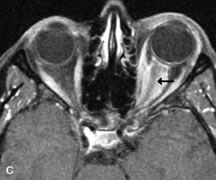

Breast carcinoma metastatic to the orbit has been demonstrated to be hypointense to the surrounding orbital fat on T1-weighted studies and hyperintense on T2-weighted images and has an affinity to the extraocular muscles (Fig. 20).50,64 The MRI characteristics of prostate carcinoma metastatic to the orbit have been described as involving the greater and lesser wing of the sphenoid, orbital roof, and optic canal. Diffuse bone hypertrophy with isointense or slightly hyperintense tissue on T1-weighted images represents the osteoblastic carcinomatous bone infiltration. Contrast enhancement is variable on T1-weighted and fat-suppressed images.65

Fig. 20. A. T1-weighted MR scan demonstrates nodular enlargement of both medial rectus muscles (arrows). B. T1-weighted fat-suppressed contrast-enhanced scan confirms the presence of small metnstatic deposits within the muscles (open arrows).